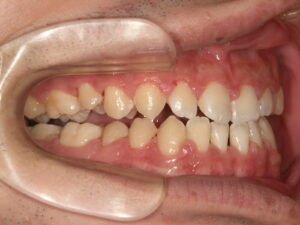

① 治療前

受け口(反対咬合)の状態です。下顎が前方に突出しています。